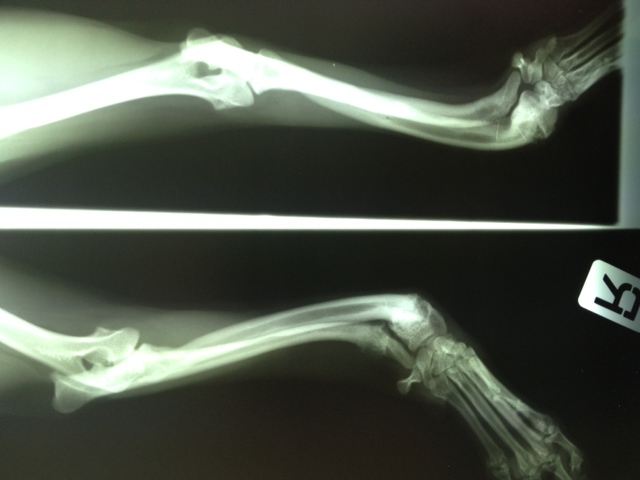

Heute hatte Felipa ihren ersten OP-Termin.

Wir waren alle sehr aufgeregt. Und selbst der erfahrene Arzt meinte, es sei eine ungewöhnliche Aktion, denn normalerweise weist nur ein Pfötchen so starke Anomalien auf. Er hatte es noch nicht, dass beide operiert werden müssen.